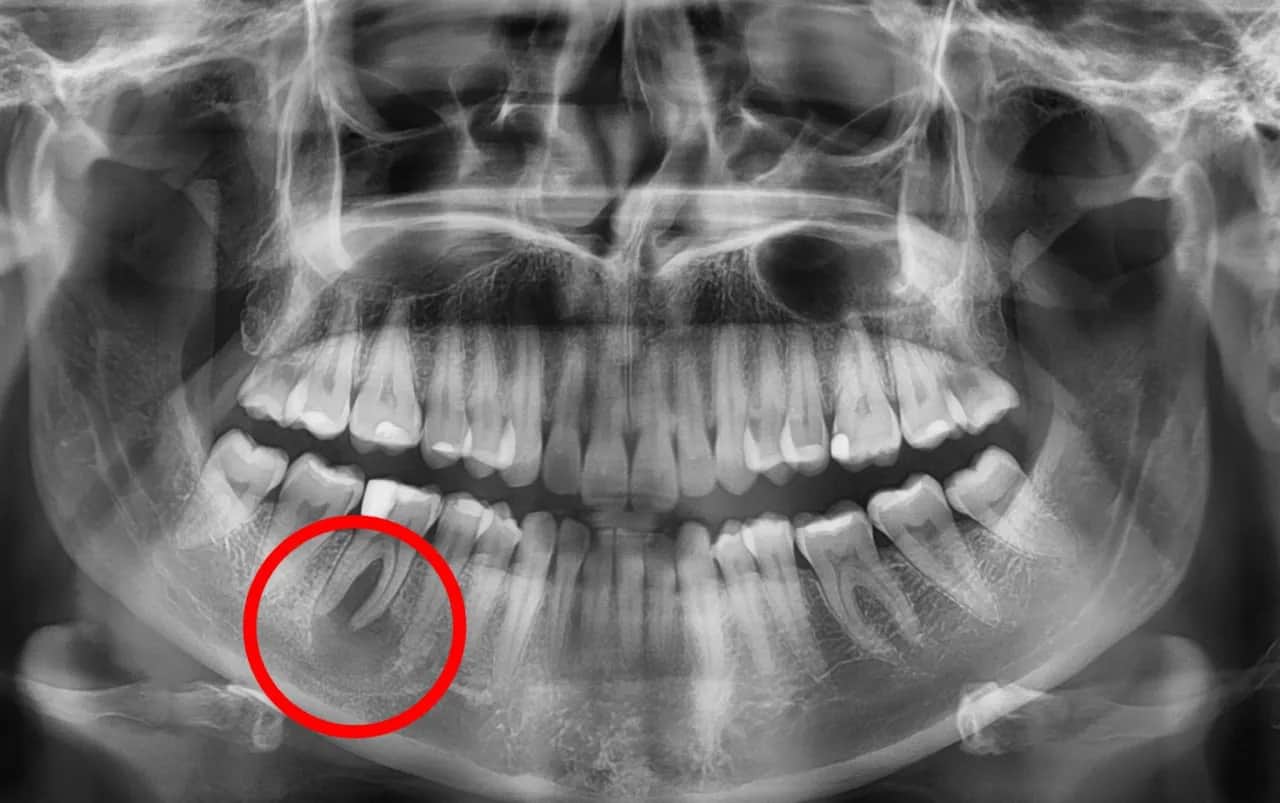

Rola przypadkowych zdjęć RTG w diagnozowaniu ukrytych zmian

Właśnie ze względu na bezobjawowy przebieg, rutynowe zdjęcia rentgenowskie odgrywają kluczową rolę w diagnozowaniu torbieli. Bardzo często torbiel jest wykrywana przypadkowo, podczas wykonywania pantomogramu (zdjęcia przeglądowego wszystkich zębów) lub zdjęcia punktowego zęba, które zlecane są z zupełnie innych przyczyn na przykład przed leczeniem ortodontycznym, protetycznym, czy podczas ogólnej kontroli. To właśnie te "przypadkowe" odkrycia ratują zęby i zapobiegają poważnym powikłaniom, ponieważ torbiel zostaje zlokalizowana, zanim zdąży narobić dużych szkód i wywołać ból.

Rola zdjęcia RTG: co stomatolog widzi na pantogramie?

Podstawowym narzędziem diagnostycznym, które pozwala mi zidentyfikować torbiel, jest zdjęcie rentgenowskie (RTG). Wykonujemy zarówno zdjęcia pantomograficzne, które dają przegląd całej szczęki i żuchwy, jak i zdjęcia punktowe, precyzyjnie obrazujące konkretny ząb i jego okolice. Na zdjęciu RTG torbiel jest widoczna jako wyraźne, okrągłe lub owalne przejaśnienie w strukturze kości, często z wyraźnymi, gładkimi granicami. To właśnie dzięki RTG możemy wykryć wiele bezobjawowych torbieli, które w innym przypadku pozostałyby niezauważone.